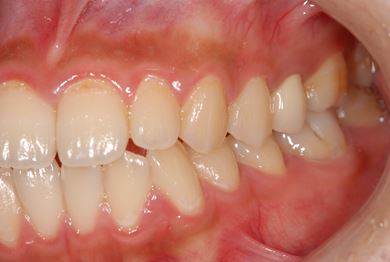

治療後

• 治療後